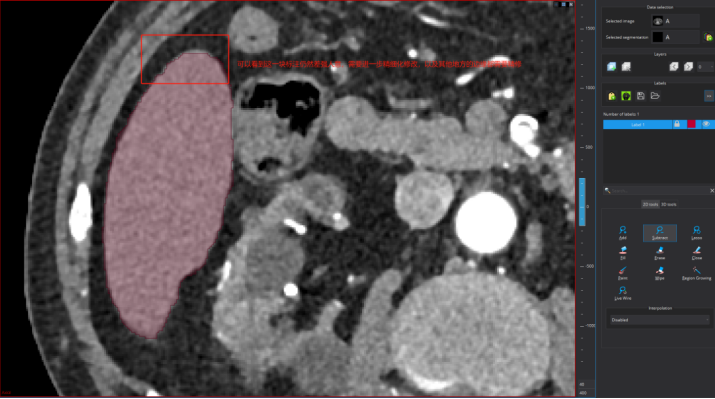

点击之后可以进行标注了,这个地方可选择的标注工具比较多,下图框出部分即为标注相关工具,标注者需要进行摸索尝试一下!需要用什么标注工具,选择一下即可,然后在图上进行标注及修改

标注示例

下面我进行标注一层进行展示,以更快学习使用,还是分步骤实现吧!(以标注肝脏为例子)

Step 1:点击标注工具add

Step 2:沿着标注目标边缘勾勒

以看到我的勾勒超出肝脏区域了,此外标注的颜色太浓会影响我对标注边界的判断。所以需要对标注进行:1)淡化标注颜色;2)修改标注。

针对问题1,调节标注颜色透明度:

针对问题2:点击下图按钮,然后沿着超出边界部分边缘进行勾画即可消除超出区域(注意:如果是标注不足,则是点击add,对不足区域的边缘进行勾画即可补上不足区域)

修改后的标注如下图所示: